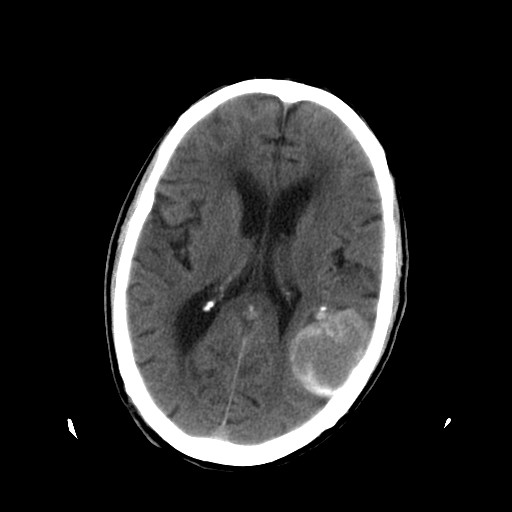

患者,男,70岁,清晨(10小时前)无法自行起床,家人无法唤醒,现昏迷,大小便失禁

左颞枕叶交界区可见类圆形高密度区,边缘可见环形更高密度影,并夹杂有点状钙化影,占位效应明显,未见明显水肿影,考虑脑膜瘤出血

肿快呈以等密度为主的等高密度影,占位效应不是很明显,只是左枕角受压,肿块内侧似有低密度改变.

左颞枕叶交界区可见类圆形高密度区,边缘可见环形更高密度影,侧脑室后角明显受压而周围未见明显水肿.考虑脑膜瘤伴出血可能性大不排外血管畸形.建议mr进一步检查.

左侧颞枕叶交界区见类圆型等高密度混杂影,边缘可见高密度影环绕,同侧侧脑室后脚受压变形,周边围见明显水肿影. 结论:脑膜瘤首先考虑.

左颞枕叶交界区的类圆形高密度区首先考虑脑膜瘤卒中,病人左侧小脑半球的还有多个囊性低密度,要考虑同时伴有梗塞的可能。

这个病人做ct时已经10小小时了,按说出血多稳定了,这么少的出血和这么小、少的梗塞怎么会导致病人昏迷?而脑干、脑桥和中脑都没有发现出血或梗塞,也没有明显的颅内高压,真的很奇怪。